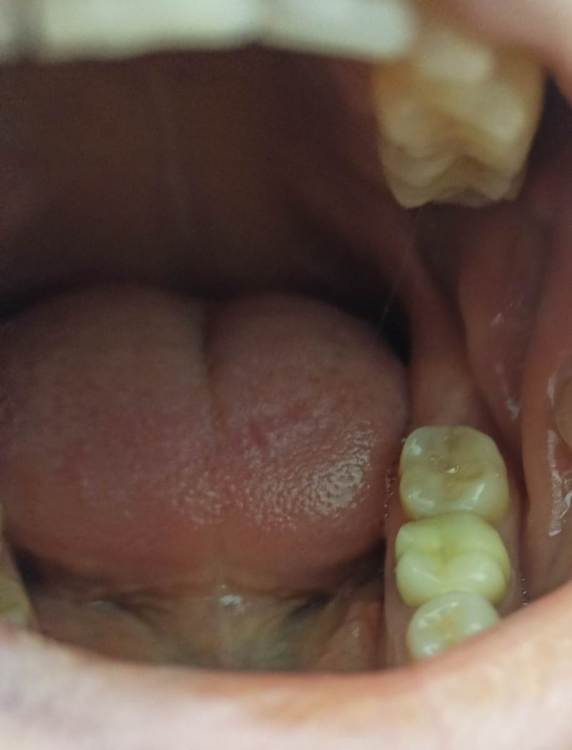

Котенька Опубликовано 10 июня, 2023 Автор Поделиться Опубликовано 10 июня, 2023 Прилагаю фото,вдруг будет более информативно. На фото с правой стороны все зубы мудрости есть,сверху кариес.На левой стороне нет. Ссылка на комментарий

Котенька Опубликовано 10 июня, 2023 Автор Поделиться Опубликовано 10 июня, 2023 (изменено) С другой стороны на верхнем зубе мудрости кариес и многие платные врачи сказали лучше удалить,тк нормально не подобраться.Но в поликлинике врач сказала,что сможет вылечить и что кариес там не большой. На нижних зубах довольно широкие пломбы. И вот сейчас думаю,удалять ли мне с другой стороны или оставить? Один терапевт сказал,что нужно удалять с двух сторон,тк пойдет ассиметрия.Не знаю что делать теперь. Изменено 10 июня, 2023 пользователем Котенька Ссылка на комментарий

Irouil Опубликовано 10 июня, 2023 Поделиться Опубликовано 10 июня, 2023 Не слышал никогда сколько нибудь вразумительных доводов о пользе симметрии в зубных рядах. На фото видно не все, но с большой долей вероятности я бы не стал рекомендовать удалять эти зубы мудрости Я полагаю что стоит ожидать улучшения ситуации слева в ближайшем будущем, Возможно причина дискомфорта в слизистой связана с чем-то другим, тут надо осматривать очно. Лечить кариес, конечно, нужно. Ссылка на комментарий